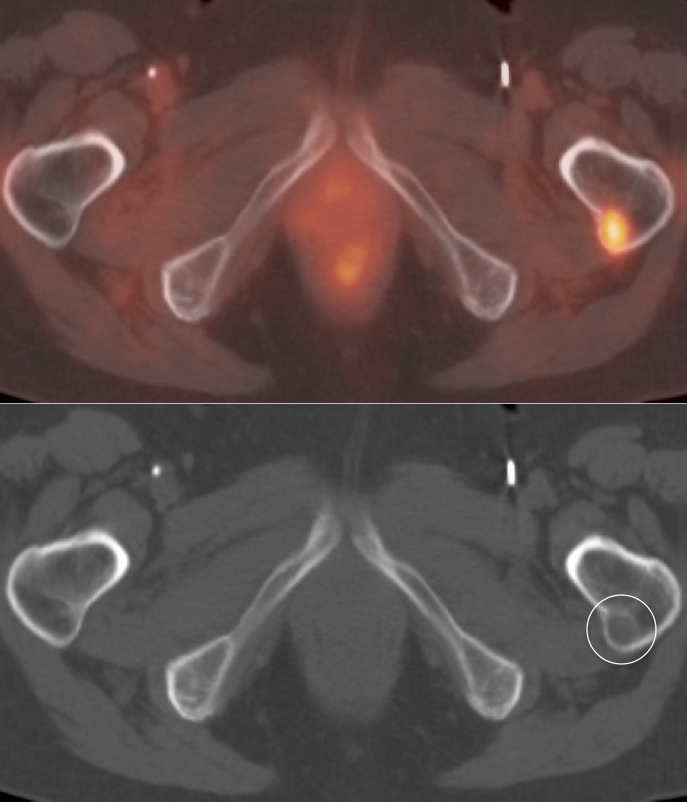

RCCA:  An Easily Overlooked Primary with PET/CT   (3 Big Limitations)

1. FDG is excreted and accumulates in the kidney, easily masking areas of pathologic uptake.

2. Many renal cell carcinomas are only mildly FDG-avid.

3. Nearly every PET/CT scan is performed without intravenous contrast, markedly limiting evaluation of the kidneys on the CT portion of the exam.

• These 3 limitations lead to a sensitivity of only ≈ 60% for the detection of a primary RCCA lesion.

Metastatic Disease: Metastatic RCCA lesions are usually more FDG avid than the primary lesion (nearly all demonstrate metabolic activity greater than liver uptake).